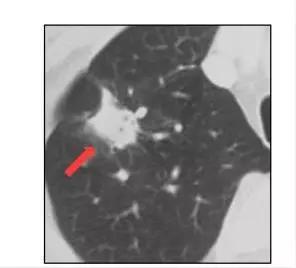

第1种情况:肺部结节变大,实性的部分增多,对于高危的“磨玻璃结节”患者,一旦结节快速长大,形态高度怀疑癌变,若大于1厘米且为实性结节者,可以考虑穿刺活检,明确诊断。快速增大直径大于1厘米但是为磨玻璃样结节,宜行手术切除。大多数病人可推荐全面微创切除,以绝后患。

第2种情况:肺部结节两次检查结果完全一致,虽然两次的结果可能都一样,但是仍然不能掉以轻心,因为光从片子上是没有办法看出良性与恶性的,建议做穿刺明确良恶性。